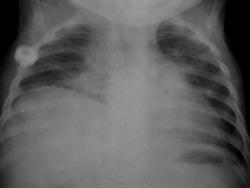

Справа высокое расположение купола диафрагмы. Рекомендовано УЗИ органов брюшной полости.

Ну во втором случае по боковой, на ателектаз похоже

И опять правый главный бронх плохо виден.

Всех смотрел на скопии. Куполы диафрагмы справа неподвижны, истиный парез. Понять, есть ли Гольцкнехт Якобсона - невозможно.

В библиотеке - журнал педиатрия - 20 лет назад, номер не помню, такая же картина - описана как случай токсического пареза.

Обратил внимание, что у всех этих детей стоит подключичный катетер на стороне поражения, далее разыскал предыдущие рентгенограммы - у двух детей они были. Снимки накануне пункции - пареза нет... Вот такая ситуация... Я для себя решил, что это травма или сдавление гематомой френикуса, и стал панически бояться подключичек....